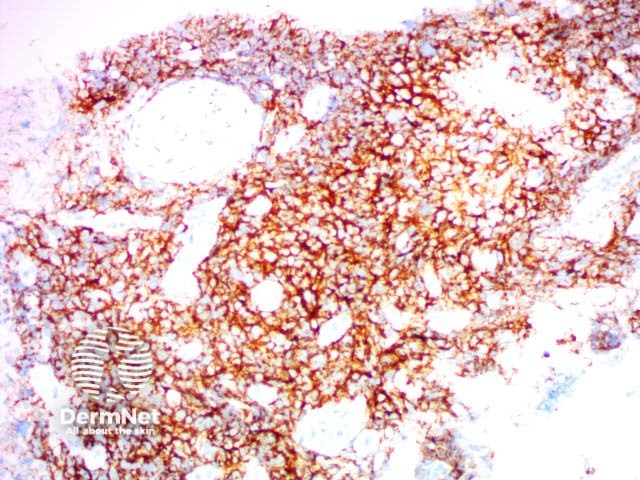

CD31 |

Helps to identify endothelial tumour |

CD34 |

Distinguishes different endothelial tumours and is positive in dermatofibrosarcoma |

CD31

CD34